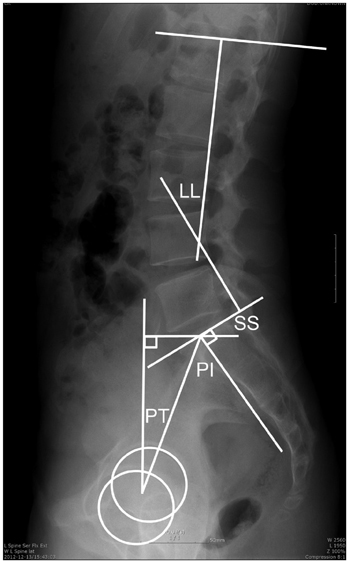

- Pelvic Incidence (PI) : ορίζεται ως η γωνία μεταξύ της κάθετης γραμμής από το κέντρο του άνω τμήματος του ιερού οστού (sacral plate) και της γραμμής που ενώνει το sacral plate με τον άξονα των μηριαίων κεφαλών. Αποτελεί ανατομική παράμετρο, καθώς είναι ξεχωριστή για τον καθένα και δεν επηρεάζεται από την θέση της λεκάνης. Προσδιορίζει την ευθυγράμμιση της οσφυϊκής μοίρας της σπονδυλικής στήλης (ΟΜΣΣ). Οι έρευνες έχουν δείξει πως μικρή τιμή της PI σχετίζεται με μειωμένη λόρδωση στην ΟΜΣΣ, ενώ μεγάλη τιμή της PI σχετίζεται με αυξημένη λόρδωση.

- Pelvic tilt (PT) : ορίζεται ως η γωνία μεταξύ της γραμμής που συνδέει το μέσον του άνω τμήματος του ιερού οστού (sacral plate) με τον άξονα των μηριαίων κεφαλών, και του κατακόρυφου άξονα. Μετράει την κλίση της λεκάνης προς τα εμπρός ή πίσω.

- Sacral Slope (SS) : Ορίζεται ως η γωνία μεταξύ του άνω άκρου του ιερού οστού (I1 σπονδύλου) και του οριζόντιου άξονα. Μετράει την οβελιαία κλίση του ιερού οστού.

Από τις παραμέτρους της λεκάνης προκύπτει και η γεωμετρική σχέση

Pelvic Incidence = Pelvic Tilt + Sacral Slope (PI=PT+SS)